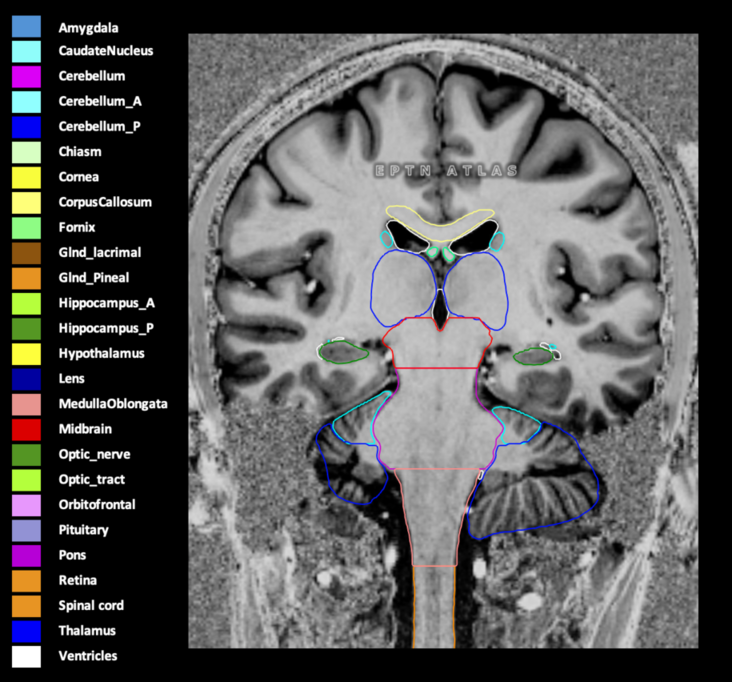

Included are all OARs known to be relevant for radiation-induced toxicity in neuro-oncology: brain, brainstem (midbrain, pons, medulla oblongata), chiasm, cerebellum (anterior & posterior), cochlea, cornea, hippocampus (anterior & posterior), hypothalamus, lens, lacrimal gland, optic nerve, pituitary, skin, and vestibular & semicircular canals. To further facilitate research on cognition, vision and radiological changes after irradiation of the brain, potential clinically-relevant OARs are included: amygdala, caudate nucleus, cerebellum (anterior & posterior), corpus callosum, fornix, macula, optic tract, orbitofrontal cortex, periventricular space (PVS), pineal gland, and thalamus.

Three-dimensional delineation of the 25 consensus OARs for neuro-oncology are shown on CT (WW/WL 120/40, 3000/600), 3T MR images, (T1Gd, T2FLAIR 1mm) and 7T MR (MP2RAGE 0.7 mm). All are presented in transversal, sagittal and coronal view.